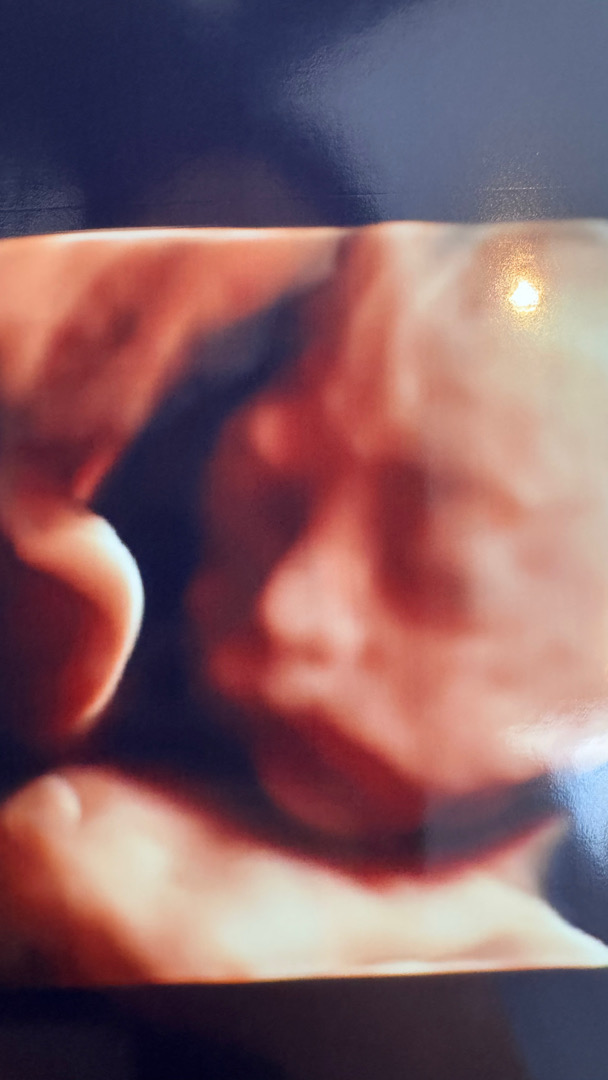

24주4일되던날 임당검사 정밀촘파를하엿어용 ㅠㅠ얼굴을바로보여주어서 역시럭키걸.. 저는입덧이1도없어서 운이너무좋다 럭키걸아야 하고서 3일뒤 임당140…..커트라인139라구 피4번뽑으러 가야합니다… 첫임당검사도 목이너무말라 힘들던데 ㅠㅠㅠㅠ너무속상합니다 아기두 800그람넘고 큰편이라구 몸무게 관리도 잘했는데 양수도많고 아이도 크다고 식사조절하라내용 내일 병원가는데 너무떨리네요…